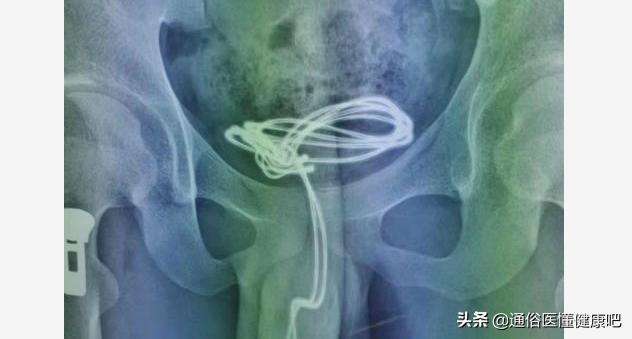

在少年尿道中段取出的异物:棉签头

这个时候,少年突然扯住我的白大褂,哭着对我说“医生,你能不能别再告诉我爸妈了,我怕他们再说我”,看着少年稚嫩和茫然无措的脸,想着昨天少年被父母“批斗”的场景,我的心一软,于是我并没有让少年父母去交费,而是支开了他们,独自带着少年往膀胱镜检查室走去,同时交代同事办理了医院留观的一系列手续和缴费。最终验证了我的判断,在相关科室其他医务人员的辅助配合下:我取出了残留在少年尿道中段,2公分左右,已经变色发黄和沾满分泌物的棉签头。